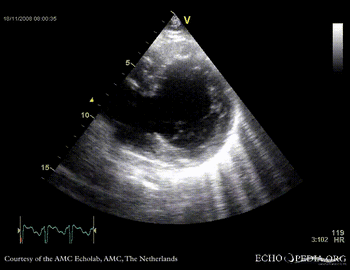

Rupture of the ventricular septum

VSR 8